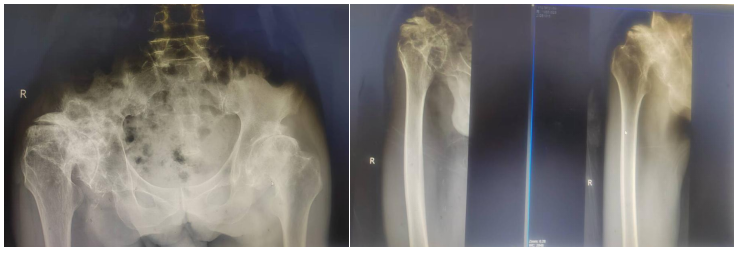

梁某某因双髋部疼痛10余年,反反复复,期间在当地医院进行过保守治疗,但是都没有取得很好的效果,尤其是近半年,患者右侧髋部疼痛症状加重,右下肢短缩、髋部活动受限,行走困难,严重影响日常活动。为了进一步治疗,在家人的陪同下慕名来到我院骨二科进行治疗。办理住院后,患者完善相关检查后,确诊为双侧髋关节发育不良,右侧严重。此症状保守治疗效果不佳,行全髋关节置换手术治疗是目前最有效的方法。但患者因长期的髋关节发育不良,导致髋关节周围肌肉韧带张力失衡、挛缩,髋关节解剖中心移位伴随脱位,髋臼侧畸形及骨量缺失等情况,手术难度较大,手术出现除普通髋关节置换的感染、血栓风险外,更容易出现假体脱位、假体周围骨折、神经血管损伤等并发症,这些都是需要考虑的问题。骨二科主任谢宝林组织科内医护人员对病例进行讨论,制定了详细的手术治疗方案、术后康复方案等,建议患者行手术治疗。告知患者及家属手术相关风险,他们表示理解,予行右侧全髋关节置换术,手术非常顺利,病情稳定。

▲手术前